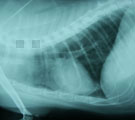

初診時レントゲン。肺野全体に広がるまだらな肺胞浸潤影。 気管支鏡検査より3日後。浸潤影はほぼ消失している。 1年2ヶ月後。この間投薬は一切なかった。肺野は正常。

経過:元気なく軽度の発熱(39.6℃)あり。5日前より突然喘息様症状あり呼吸困難もあるとのことだった。胸部レントゲンでは肺野全体に広がるまだらな肺胞浸潤影がみられた。動脈血酸素分圧は79.2mm Hgとやや低下し軽度の肺機能低下がみられた。感染による肺炎が疑われたが、腫瘍や猫喘息との鑑別の必要もあり気管支鏡検査を行った。粘膜は全体的に浮腫状を呈していた。気管支肺胞洗浄液(RB3, 回収率76.7%)中に細菌・真菌は検出されなかったが好中球の増加(60.25%)がみられた。腫瘍細胞はみられず、喘息を示唆する好酸球もみられなかった。無菌性の気管支肺炎であった。入院にて酸素、気管支拡張剤、去痰剤を投与し、治療初期にのみ抗生剤を投与した。検査より3日後には肺野の浸潤影はほぼ消失し元気食欲がでできた。10日後退院。それから1年2ヶ月後、腫瘍摘出の件で入院した際の胸部レントゲンでは肺野は正常化していた。この間投薬は一切なかった。